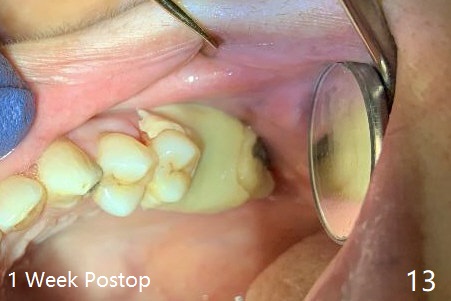

A 57-year-old woman complains of bad smell while use of water flosser between 11 and 21 months post cementation of implant crown at #14 (Fig.1,2). Bone loss is more obvious with CBCT (Fig.3,4), in spite of apparently normal gingiva around the implant after removal of the abutment and crown (Fig.5). In fact the buccal (B) gingiva is fragile with easy access to the underlying implant plateau. Following flap elevation, the bone loss is evident (Fig.6), but the implant plateau is slightly subcrestal (Fig.7 *). The exposed implant threads are covered with the 1st round of bone graft (Fig.8). After 2nd round of allograft (Fig.10-12) and collagen membrane, the flaps are approximated (Fig.9). The wound is covered by acrylic dressing. The latter is loose, but stays in place 1 week postop (Fig.13). Due to short neighboring teeth, the acrylic dressing is able to be removed with wiggling; it appears that the wound is healing (Fig.14). The dressing returns for another 2 weeks; some of the graft has been lost (Fig.15). The dressing does not return 7 weeks postop, since the wound is healing (Fig.16).